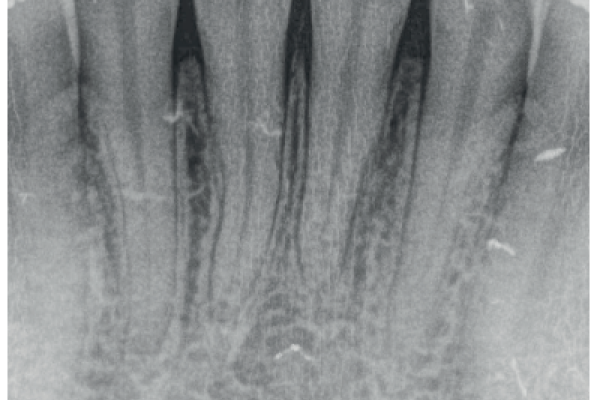

Tratamiento de recesiones gingivales unitarias y múltiples en la zona anterior mandibular mediante técnica de Edlan-Mejchar modificado. Descripción de la técnica quirúrgica y resultados